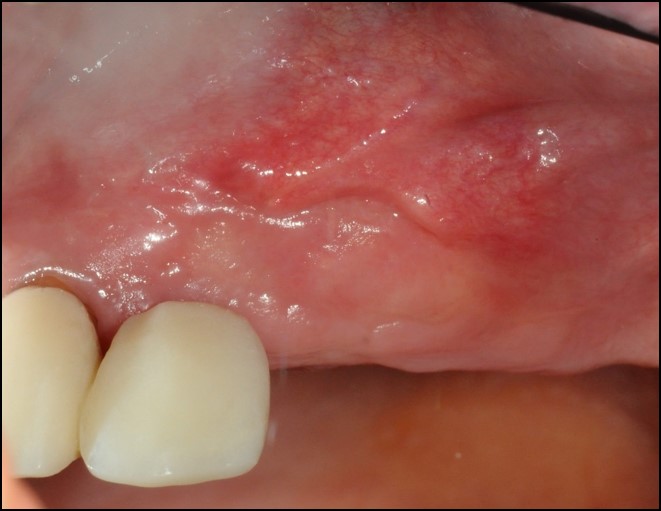

9/9 - Newly formed keratinized mucosa 6 months post-operativeWidening of the peri-implant keratinized mucosa in the upper jaw with mucoderm®- Dr. A. Horváth